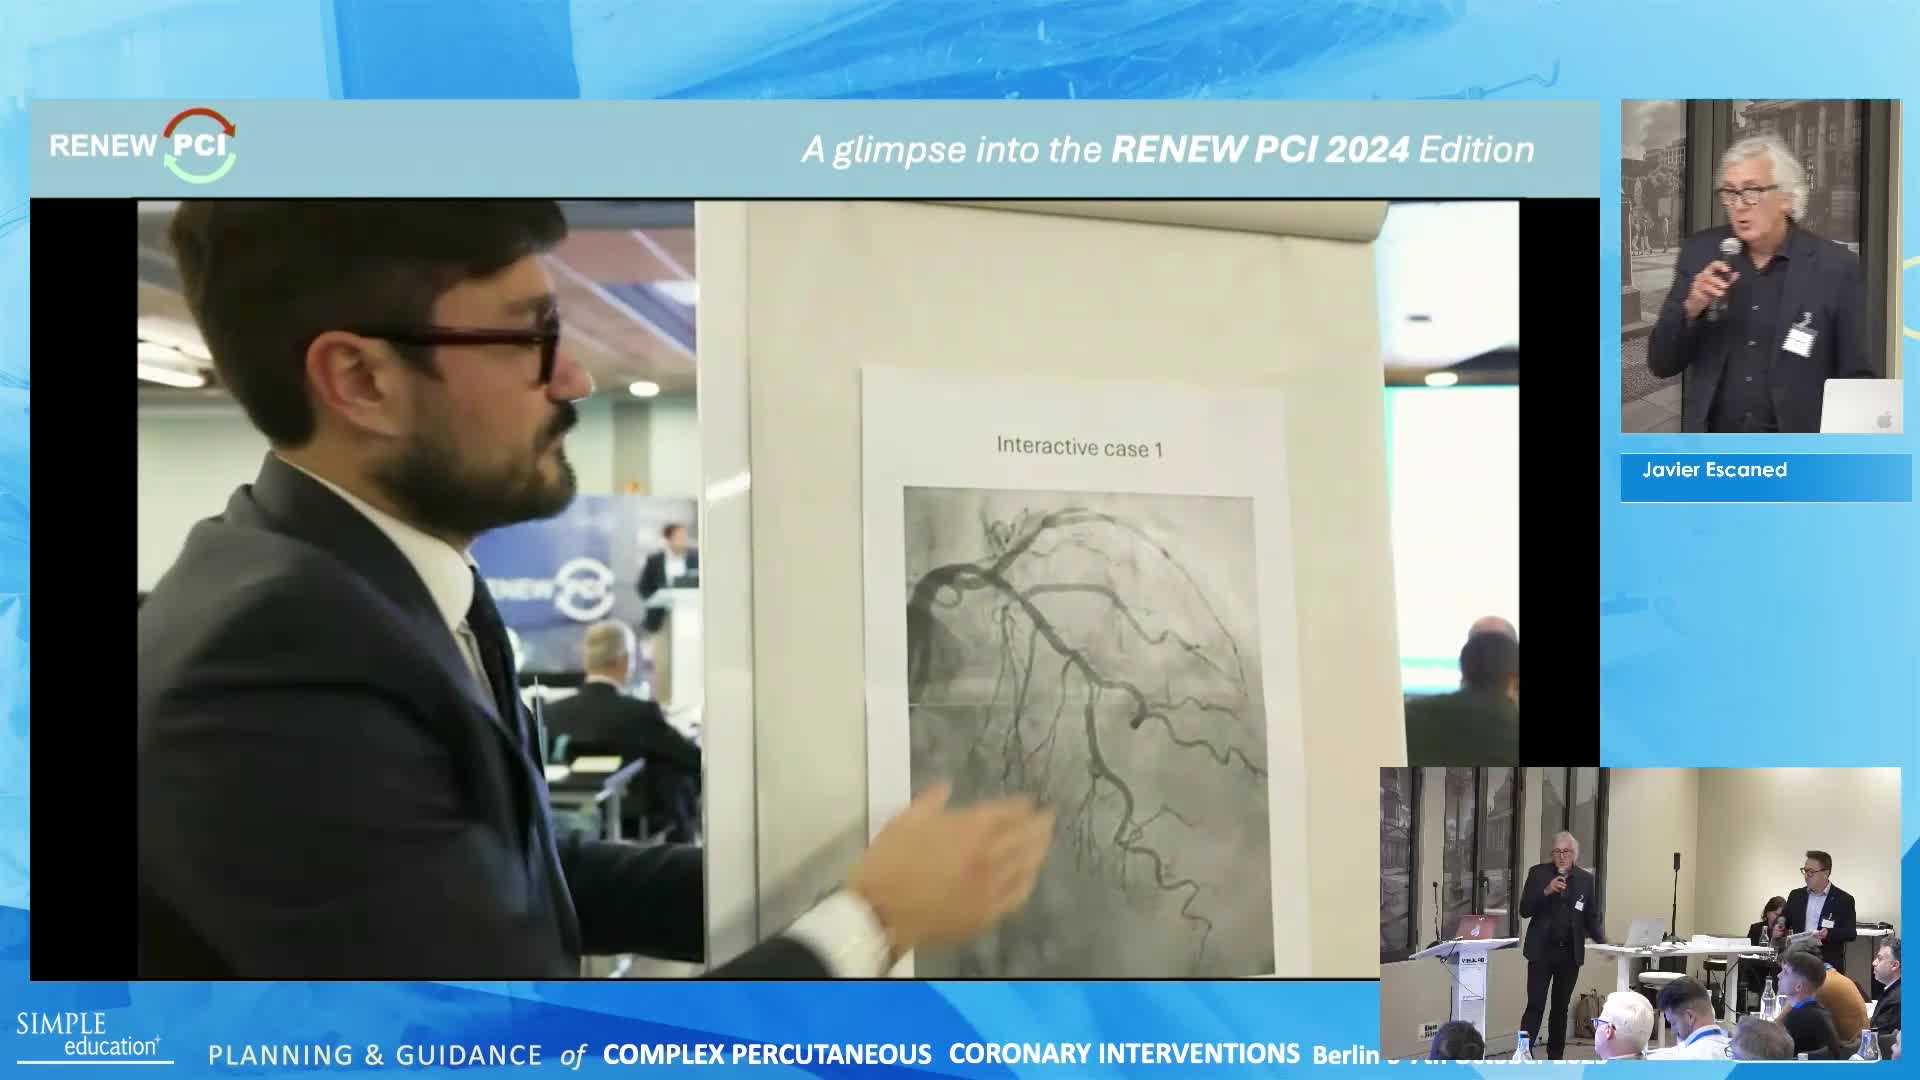

Planning and guidance of complex percutaneous coronary interventions - June 2023 Day One

Planning and guidance of complex percutaneous coronary interventions - June 2023 Day Two

Planning and guidance of complex percutaneous coronary interventions - October 2022 Day One

Planning and guidance of complex percutaneous coronary interventions - October 2022 Day 2

Planning and Guidance of Complex Percutaneous Coronary Interventions - May 2022 Day One

Planning and Guidance of Complex Percutaneous Coronary Interventions - May 2022 Day Two

Best practices and personalised medicine in complex PCI - Prof Javier Escaned

Essential steps for physiology-based PCI planning and guidance - Dr Allen Jeremias

Intracoronary guidance in acute coronary syndromes - Dr Hernan Mejia-Renteria

Functional assessment of coronary stenosis prior to TAVI - Prof Flavio Ribichini

Coronary Bifurcations: An Update on Diagnosis, PCI planning and Imaging and PhysiologyGuidance - Dr Dejan Milasinovic

Revascularisation in stable angina: a contemporary perspective - Dr Rasha Al-Lamee